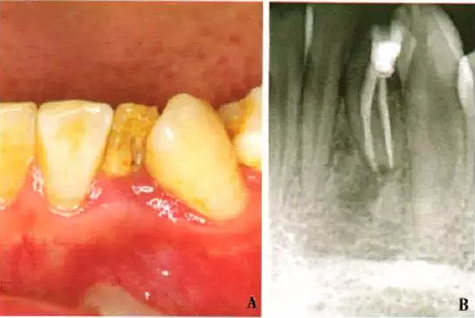

1周后,患者述疼痛消失。復(fù)診采用冷測壓方法根管充填(圖2),牙冠開髓孔處應(yīng)用Chem—flex(DentsplyDeTreyGmbH,Konstanz,Germany)充填。由于患牙牙冠形態(tài)異常,且唇側(cè)形態(tài)尚未恢復(fù);患牙周圍有牙石、軟垢,建議患者行牙周及修復(fù)治療以維持長期療效,被患者拒絕。9個月后隨訪,患者自述患牙經(jīng)治療后無癥狀,臨床檢查見32叩診正常,無松動;影像學(xué)檢查見32根尖周圍透射區(qū)域明顯減?。▓D3)。

A:32口內(nèi)像;B:X線片示32根尖周炎癥明顯減輕

圖3 左下側(cè)切牙9個月隨訪檢查